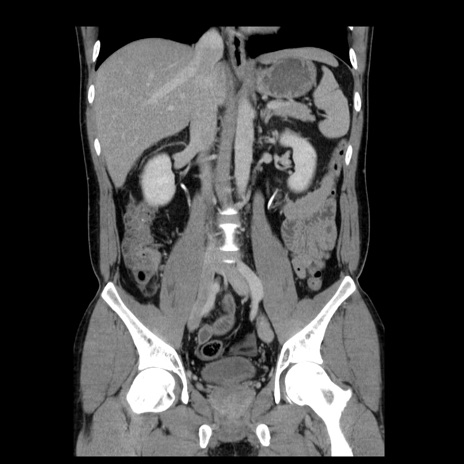

症例4(冠状断像)

【症例】30歳代男性

【主訴】腹痛、嘔吐

【現病歴】昨晩から突然の腹痛あり、その後嘔吐、軟便も出現。腹痛が改善しないため救急搬送となる。2日前にしめ鯖の食事歴あり。

【身体所見】意識清明、苦悶様、BP 135/90mmHg、BT 35.7℃、腹部:平坦、やや硬、心窩部〜臍部に自発痛、圧痛あり、筋性防御+、反跳痛-

【データ】WBC 8100、CRP 0.57